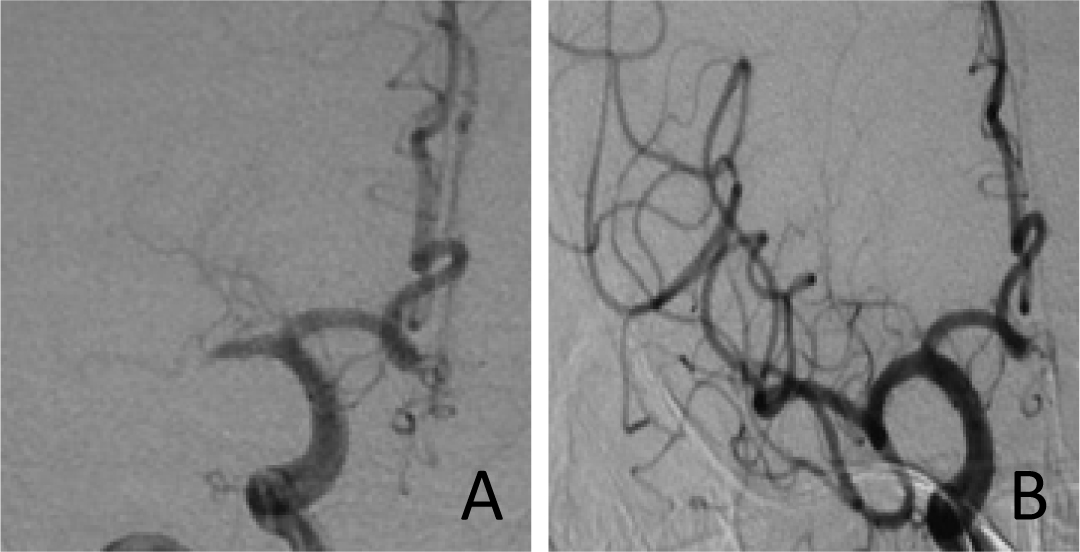

Recanalization images from 3 cases are presented in Figure 1 ~ 3. The preoperative TICI grading of these 15 patients were all level 0. After the thrombectomy, 14 patients were level 2b to level 3. However one ipsilateral cervical carotid occlusion patient demonstrated failure to recanalization.

Patient 1:The MCA Ml occlusive images before and after treatment. In 1a, preoperative DSA imagine is shown on the right side of the MCA M1 occlusion. In 1b, solitaire stent thrombosis after immediate review imaging, the right MCA show stotally recanalization and the TIMI grade was3.

Patient 2 :The MCA M1 occlusive images before and after treatment. In 2a, preoperative DSA imagine is shown on the right side of MCA M1 occlusion. In 2b, imagine displays that the MCA completely was recanalizated.